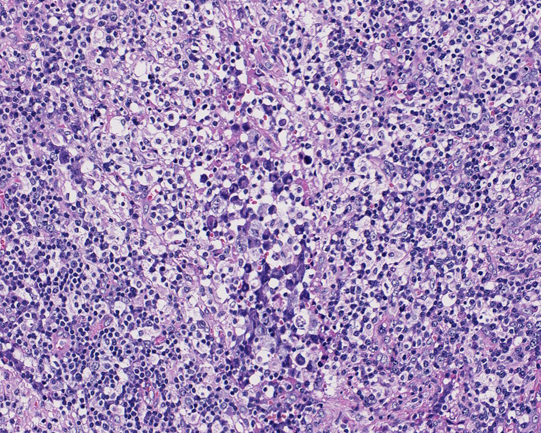

20歳 鼠径リンパ節

左臀部の痛みで発症する。臀部軟部組織に腫瘤を認めCTで腸骨, 大腿骨の欠損あり。左鼠径, 大動脈周囲, 後腹膜, 骨盤内腔のリンパ節が腫大し脾腫、胸水腹水の貯留を認める。WBC 15500/cmm, LDH 470(<350), sIL2-R29100U/ml

リンパ節組織所見

大型異型細胞が集簇し結合性に増殖している。未分化癌や悪性黒色腫が鑑別となる。細胞は大型で類円形, 楕円形核に加えて腎臓様の特異な核形を示す。